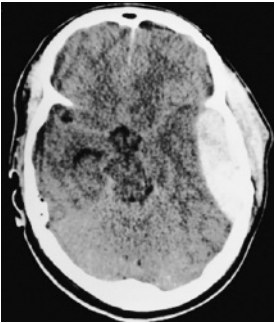

Paciente do sexo masculino, 23 anos, foi vítima de acidente automobilístico no qual o veículo em que estava colidiu com caminhão. Usava cinto de segurança e foi retirado consciente do carro pela equipe de resgate. Apresentava amnésia anterógrada. Após atendimento pré-hospitalar, o paciente foi levado ao pronto-socorro, sem déficits motores ou sensitivos. No hospital, o médico pede uma tomografia computadorizada de crânio para avaliação. Alguns minutos depois, a equipe de enfermagem solicita avaliação de emergência para o paciente, com necessidade de intubação orotraqueal por rebaixamento do nível de consciência e anisocoria com pupila esquerda dilatada. Tomografia computadorizada de crânio sem contraste

Ao considerar a situação clínica do paciente e a imagem tomográfica apresentada, o médico diagnosticou